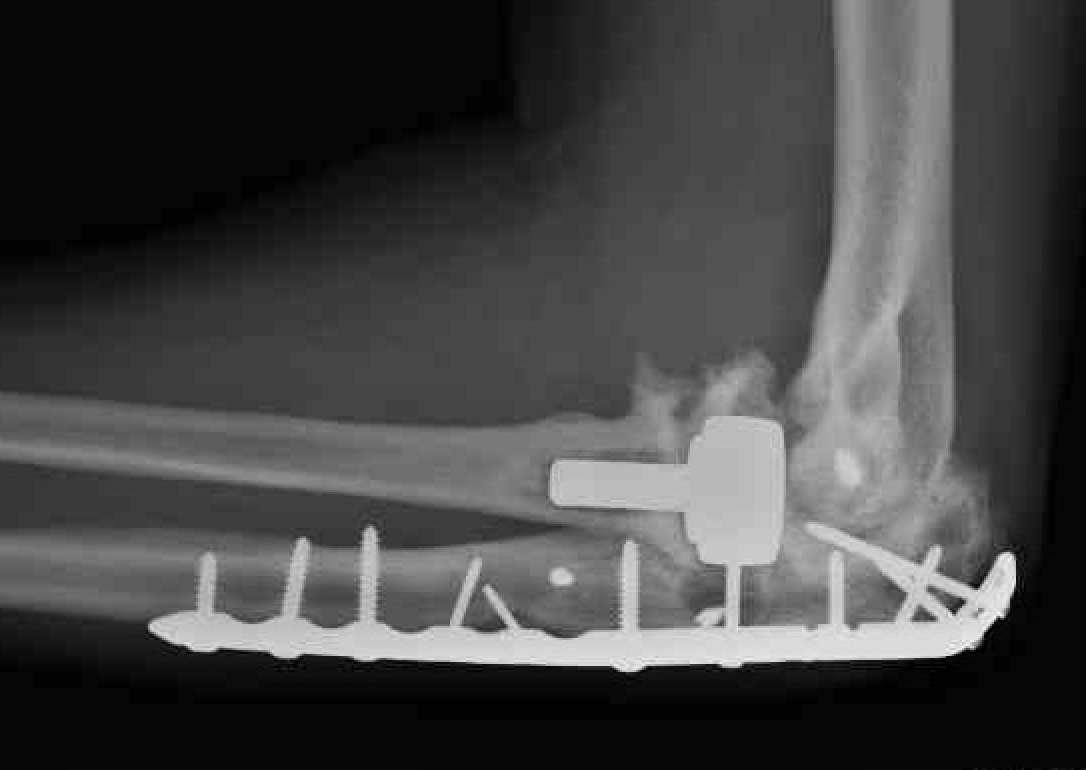

Complex proximal ulna fracture with radial head replacement subluxation